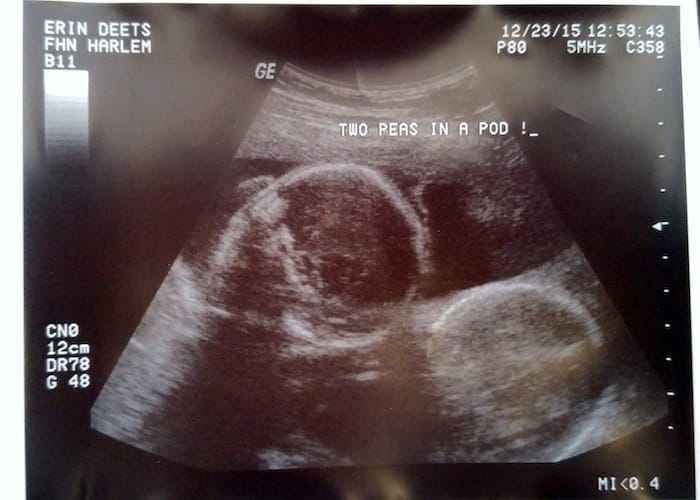

Ultrasound Photos at 21 Weeks Pregnant With Twins